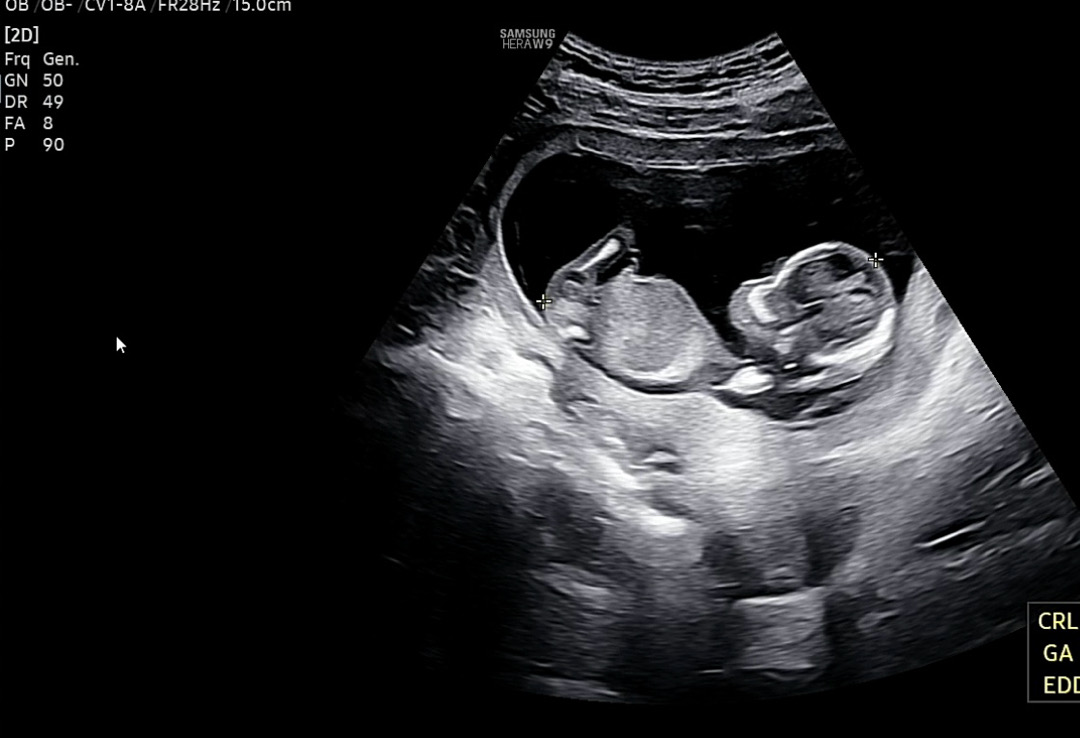

제발 성별 좀 봐쥬세요오ㅠㅠ

아들일까요 딸일까요 ㅠㅠㅠ 너무 궁금해용..👼🏻

잘 안보이는거같아요